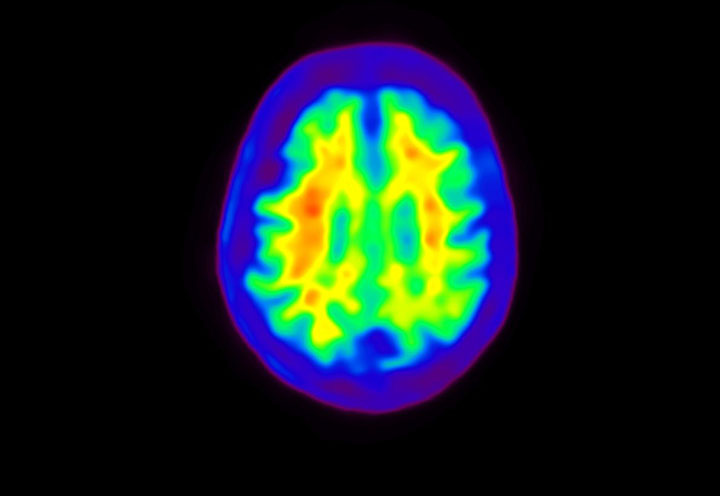

Head / Case4 : Amyloid

Axial

Courtesy : Kindai University Hospital

- Imaging protocol

- Injected dose: 3.21 MBq/kg, 18F-Flutemetamol

- Uptake time: 100 minutes

- Scan time: 20 minutes